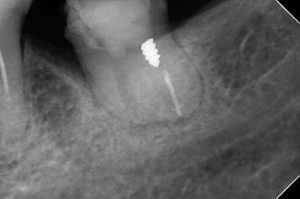

たとえば、下顎左側第二大臼歯の近心根に破折ファイルが認められます。

自発痛が強く、他院では抜歯してインプラントを勧められました。

当院で破折ファイルを除去したところ、とても喜んでくださいましたが、